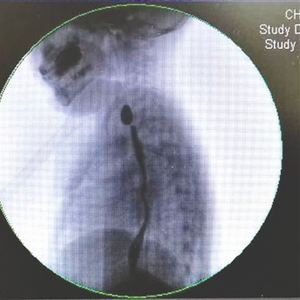

李勇刚介绍,彤彤到儿童医院接受治疗后,医院对其进行了3次食道扩张手术,但每次扩张后仅几天便出现收缩,效果不佳。9月12日,医院为彤彤实施了食道支架置入手术,在她的食道内置入了全覆膜食管支架,使得食管腔明显增大。如顺利,6个月后,该支架将取出。

2016年,美国两岁男童Logan Stiff在托儿所误吞下一块遥控器中的纽扣电池(左图),电池烧穿他的食道,影响气管膜壁,导致Stiff可能失去发声能力。当时Stiff出现了未知原因的呕吐症状,Stiff的父母迅速把他送去了医院。